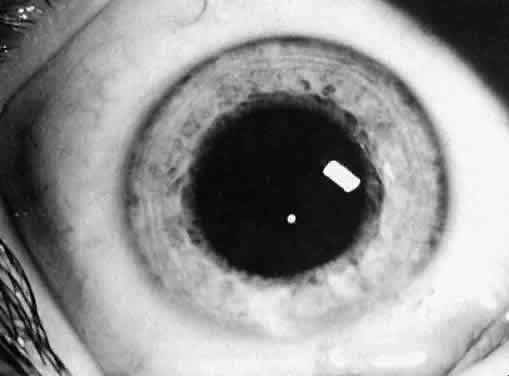

Not all cataracts require surgical treatment. Eyes with punctate or small anterior polar cataracts and others with partial opacification of the lens, such as posterior lenticonus, which only slightly interferes with the refraction of light, are best followed and not surgically treated (Fig. 1). In some cases, it is difficult to determine whether the presence of a partial cataract is responsible for a decrease in visual acuity or whether the refractive error or optical distortion produced by the cataract has produced a mild, reversible form of deprivation amblyopia. In these situations, correction of the refractive error and a trial of occlusion therapy should be attempted. If the visual acuity improves, it may be deduced that amblyopia was responsible for the loss of visual acuity and that the optical distortion produced by the partial cataract is not yet surgically significant.

Fig. 1. Cataracts that do not require surgical treatment. A. Anterior polar cataract. Visual acuity is 20/25. B. Partial punctate or cerulean cataract. Visual acuity is 20/30.